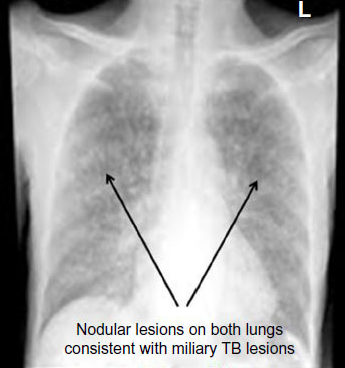

- Miliary TB: rupture of caseous pulomnary focus into blood vessel so widespread dissemination through body

What does a CXR of TB look like?

What are some extra-pulmonary signs of miliary TB?